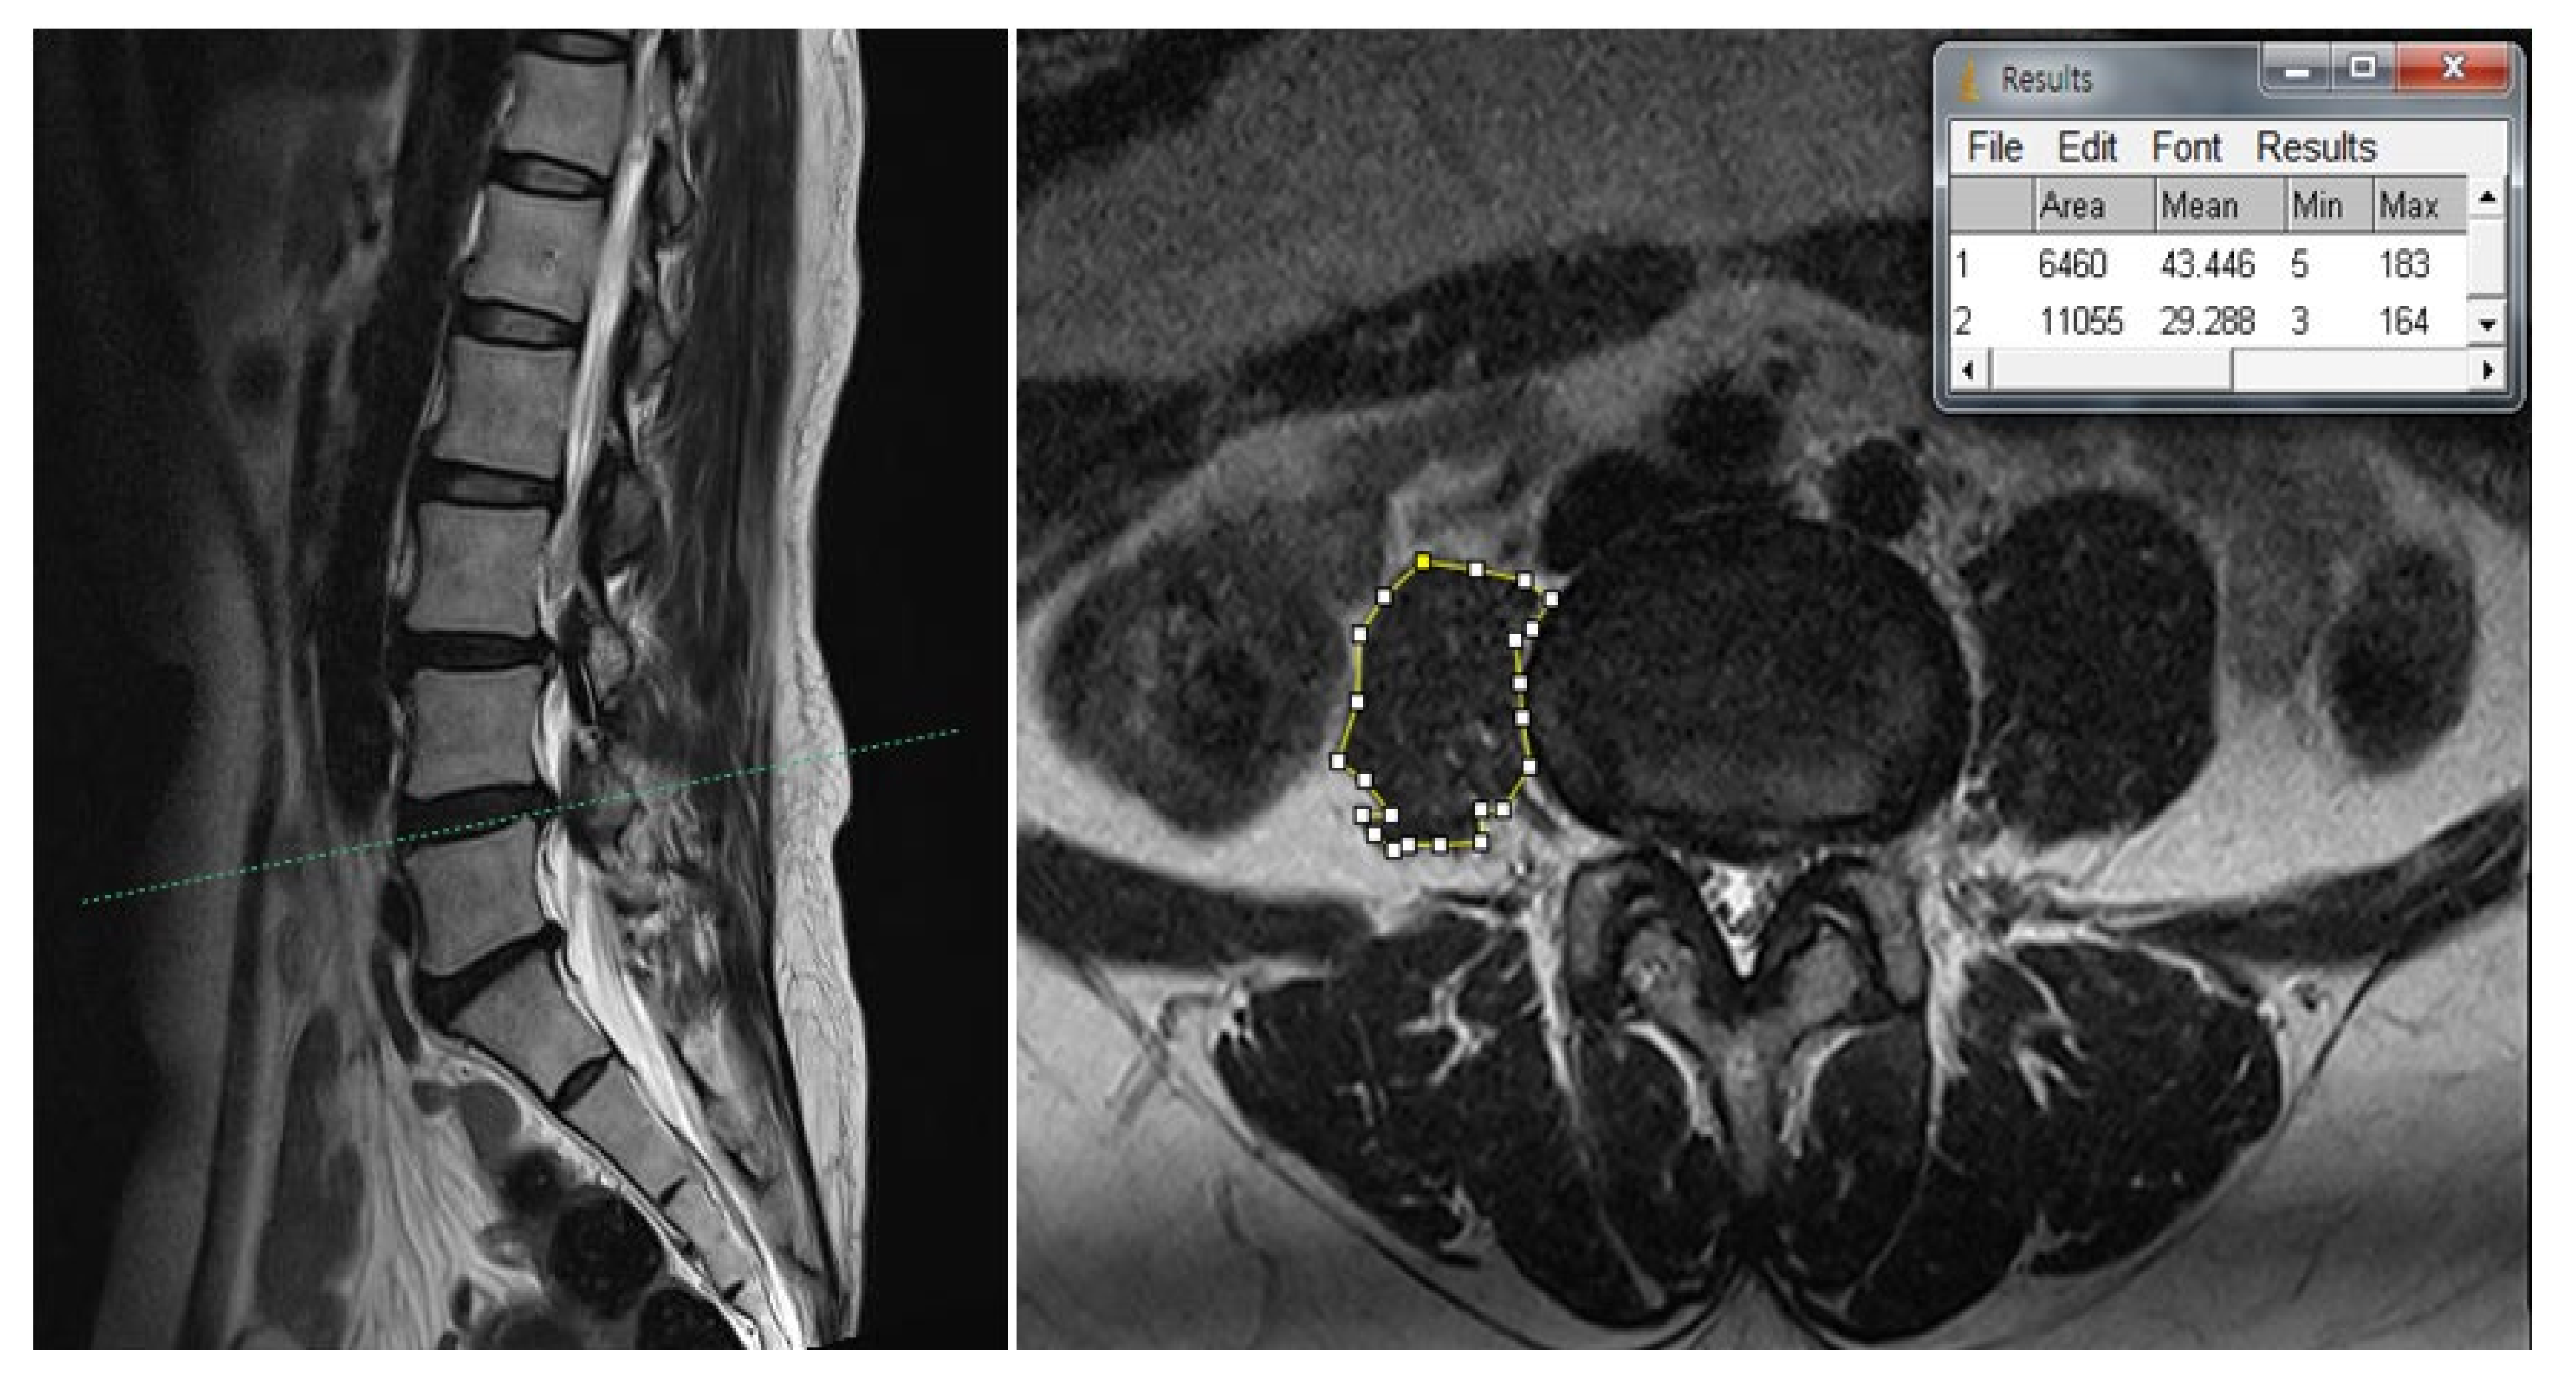

2. Case